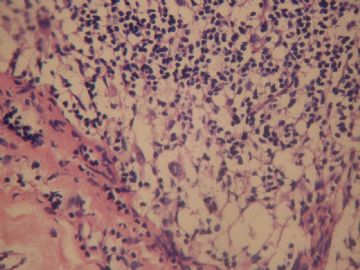

• 左颈淋巴结肿大图4

图4

淋巴窦明显扩张,窦内组织细胞增生,存在次级淋巴滤泡,应该是淋巴结反应性增生(以窦组织细胞为主)。

老年女性,全身多发 淋巴结肿大,图1见深染区和浅染区,图2 和3见生发中心血管植入,呈蚊香样结构,图4,5见组织细胞增生,未见吞噬现象,淋巴结髓索和窦境界存在,见滤泡结构,首先考虑淋巴结反应性增生病变(窦性增生),但要排除castlamen病可能

老年女性,全身多发 淋巴结肿大,图1见深染区和浅染区,图2 和3见生发中心血管植入,呈蚊香样结构,图4,5见组织细胞增生,未见吞噬现象,淋巴结髓索和窦境界存在,见滤泡结构,首先考虑淋巴结反应性增生病变(窦性增生),但要排除castlamen病可能,浆细胞不明显